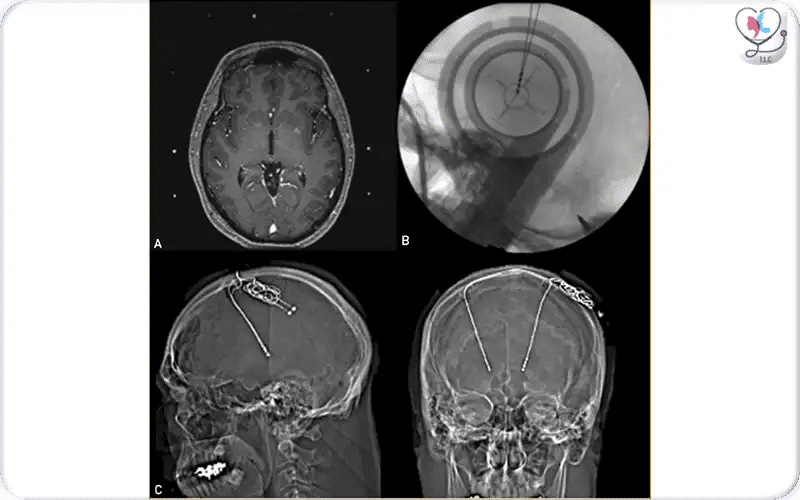

This image shows the use of imaging during DBS surgery. Intraoperative MRI (A) helps the surgeon plan the exact placement of electrodes in the thalamus to treat essential tremor. Fluoroscopy (B) confirms accurate positioning of the electrodes during surgery, and postoperative CT scans (C) verify their final placement, ensuring safe and effective stimulation.

Recent studies show that asleep-DBS can provide similar or better outcomes than awake-DBS for speech, cognitive function, and patient comfort. Modern MRI/iMRI/CT guidance allows precise electrode placement without relying on patient feedback. Awake-DBS is still performed in specialized centers for real-time testing of neurological function.